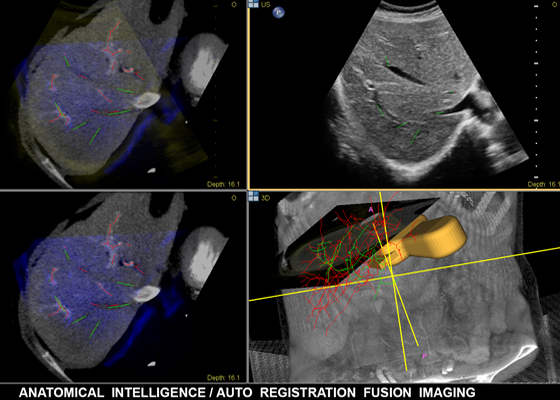

Технология Anatomical Intelligence для УЗИ использует специализированные средства моделирования органов, формирования срезов и количественного анализа, помогая упростить проведение исследований, повысить воспроизводимость их результатов и достичь того уровня клинической информативности, который соответствует современным экономическим и клиническим задачам. Технология Anatomical Intelligence применяется в таких визуализационных решениях компании Philips, как EchoNavigator, EP Navigator и HeartNavigator. Уже сегодня она дает врачам мощные, но простые в применении средства обработки и помогает им быстрее и увереннее определять анатомические структуры и нарушения, оценивать состояния заболеваний, назначать лечение и контролировать вмешательства.

Технология Anatomical Intelligence используется такик в решениях для визуализации Philips как: EPIQ, Affiniti и EchoNavigator. Уже сегодня эта технология предоставляет врачам продвинутые, но простые в использовании инструменты для обработки. Помогает им быстро и более уверенно определить анатомию и аномалии, стадию болезни, а также назначить лечение.